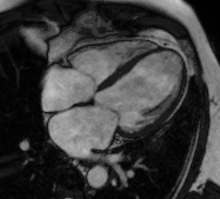

Atrial septal defect with dilation of the right ventricle by CMR

Partial Anomalous Pulmonary Venous Drainage by CMR

Enlarged right ventricle with poor function in a patient with repaired tetralogy of Fallot by CMR